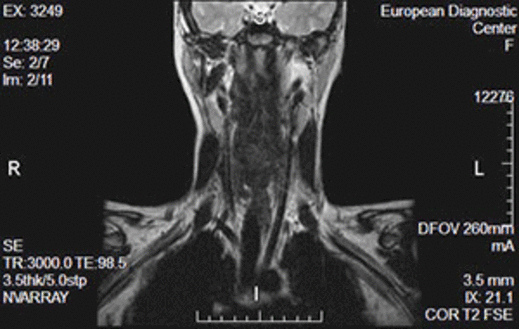

Расшифровкой снимков МРТ позвоночника занимается рентгенолог или же врач функциональной диагностики. Трехмерные карточки сравнивают со снимками здорового человека, после чего выявляют возможные патологические изменения. К ним относят: грыжу, остеохондроз и т. д. Анализ поможет определить стадию развития болезни, а также подобрать оптимальные методики лечения. На карточках можно четко рассмотреть мягкие ткани и кости — кости окрашены в темный цвет, а спинной мозг — в светлых тонах.